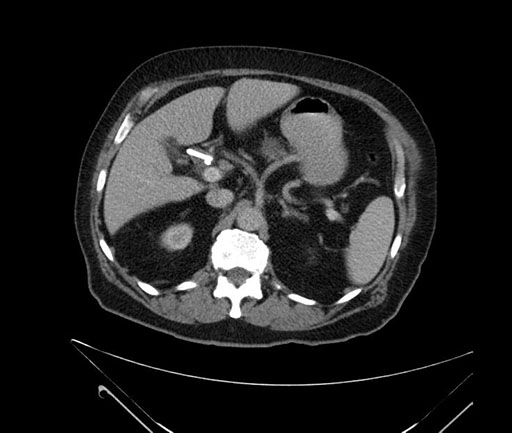

Imaging analysis

Based on your CT findings, which issue(s) would give reason for "planned slowing down moment(s)" in this case?

Considering a standard Whipple procedure, what step(s) of the operation would you do differently in this case?